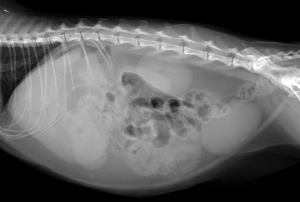

今回治療させていただいた猫ちゃんは、数日前から頻回嘔吐しており、ぐったりしているとの主訴で来院されました。レントゲン検査では、腸が手繰られた所見があり、お腹に漏れたガスも確認されました。